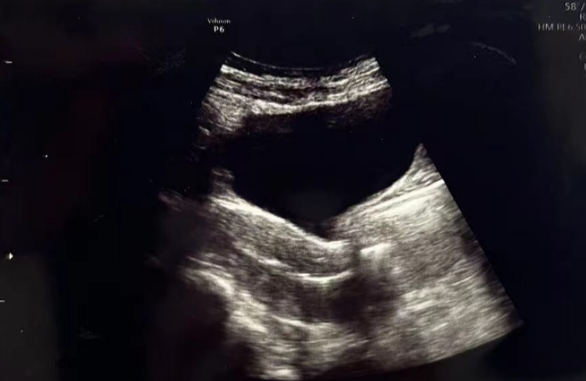

微创清积液

在进行3毫升的子宫峡部切口冲洗后,经过经腹超声检查显示子宫内膜呈三线状,且子宫腔内未见液体。

术后给予抗生素预防感染,为后续胚胎移植扫清子宫环境障碍。

• Pre-Irrigation灌洗前:

• Pre-Irrigation灌洗后: